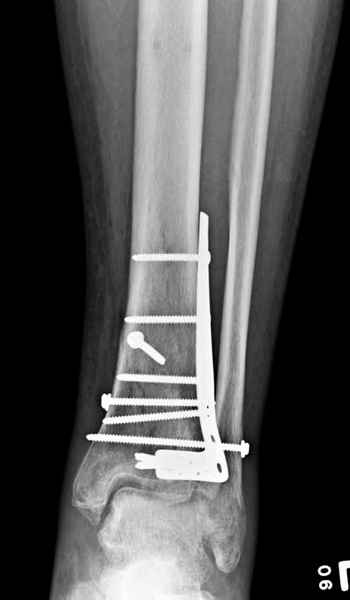

В приложении метафизарный перелом у ребёнка 14лет, с распространением линии перелома на зону роста.

В примере показан не перелом пилона, а эпифизеолиз, м/берцовую кость сознательно не фиксировал(длина её восстановлена, ротации нет),у детей стараемся минимизировать операц.травму, несколько позже разрешил полную нагрузку на ногу(4 недели). Но принцип фиксации б/берцовой кости м.б. таким же.

3. стабилизировать наружный опорный комплекс голени и предотвратить вальгусную деформацию голеностопного сустава. Конечно, данная проблема не очень актуальна, или вовсе не актуальна для 43С1, но для повреждений типа 43С2,3, особенно в случаях, когда метафизарный дефект потребовал пластики, а пластину пришлось уложить по медиальной стороне - остеосинтез малоберцовой кости является крайне необходимым - привожу характерный пример.